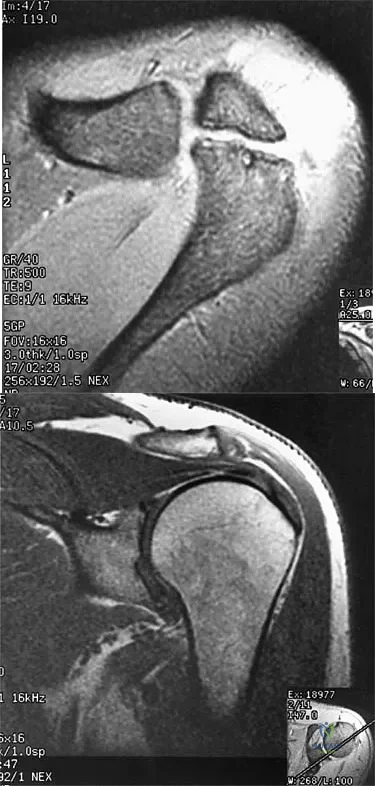

A 47-year-old male tennis player has pain in his nondominant shoulder that has failed to respond to 4 months of nonsurgical management. Examination reveals acromial tenderness and pain at the supraspinatus tendon insertion. He has a positive impingement sign, pain on forward elevation, and minimal cuff weakness. The MRI scans are shown in Figures 30a and 30b. To completely resolve his symptoms, treatment should consist of

Explanation